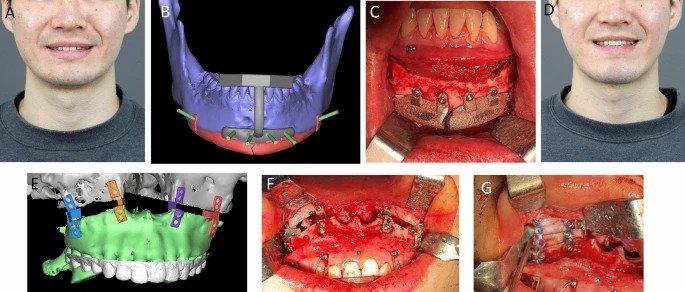

今年 5 月,一组韩国研究人员进行了一项回顾性研究,以验证 3D 打印钛种植体在颌面骨骼上的有效性和安全性。该研究观察了 16 名患有各种颌面部缺损的患者的结果,几乎所有的种植体都显示出令人满意的治疗效果。

修复手术案例研究之一。图片来自自然。

今年 5 月,一组韩国研究人员进行了一项回顾性研究,以验证 3D 打印钛种植体在颌面骨骼上的有效性和安全性。该研究观察了 16 名患有各种颌面部缺损的患者的结果,几乎所有的种植体都显示出令人满意的治疗效果。

修复手术案例研究之一。图片来自自然。